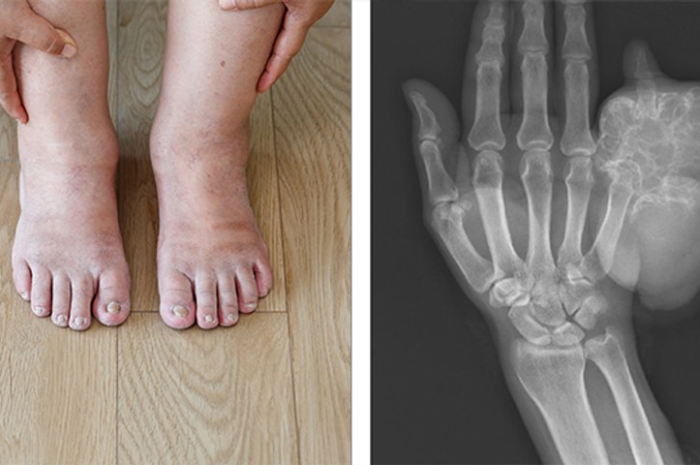

Continue Readingहड्डियों में सूजन क्यों होती है? जानें इसके लक्षण और बचाव के टिप्स । Boldsky